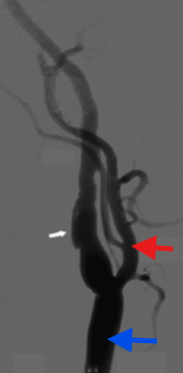

What exam is seen here?

If this was imaged at the neck, what vessel is the white arrow?

Red arrow?

Blue arrow?

Arteriogram

ICA

ECA

CCA